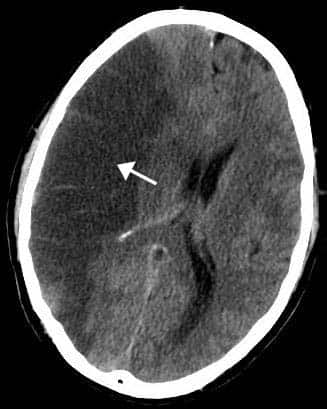

The cerebrum is the largest part of the brain, located superiorly and anteriorly in relation to the brainstem. It consists of two cerebral hemispheres (left and right), separated by the falx cerebri of the dura mater. Embryologically, the cerebrum is derived from the prosencephalon. In this article, we will look at the anatomy of the cerebrum – its structure, function, blood supply and the clinical implications of cerebral lesions. Pro Feature - 3D Model You've Discovered a Pro Feature Access our 3D Model Library Explore, cut, dissect, annotate and manipulate our 3D models to visualise anatomy in a dynamic, interactive way. Learn More Anatomical Position and Structure Database Center for Life Science and BodyParts3D [CC BY-SA 2.1 jp], via Wikimedia Commons Fig 1Anatomical position of the cerebrum. The cerebrum is located within the bony cranium. It extends from the frontal bone anteriorly to the occipital bone posteriorly. Within the skull, the cerebrum fills the anterior and middle cranial fossae, and is located above the tentorium cerebelli inferoposteriorly. Internal Structure The cerebrum is comprised of two different types of tissue – grey matter and white matter: Grey matter forms the surface of each cerebral hemisphere (known as the cerebral cortex), and is associated with processing and cognition. White matter forms the bulk of the deeper parts of the brain. It consists of glial cells and myelinated axons that connect the various grey matter areas. External Structure Externally, the cerebrum has a highly convoluted appearance, consisting of sulci (grooves or depressions) and gyri (ridges or elevations). It is divided into two anatomically symmetrical hemispheres by the longitudinal fissure – a major sulcus that runs in the median sagittal plane. The falx cerebri (a fold of dura mater) descends vertically to fill this fissure. The two cerebral hemispheres are connected by a white matter structure, called the corpus callosum. The main sulci are: Central sulcus – groove separating the frontal and parietal lobes. Lateral sulcus – groove separating the frontal and parietal lobes from the temporal lobe. Lunate sulcus – groove located in the occipital cortex. The main gyri are: Precentral gyrus – ridge directly anterior to central sulcus, location of primary motor cortex. Postcentral gyrus – ridge directly posterior to central sulcus, location of primary somatosensory cortex. Superior temporal gyrus – ridge located inferior to lateral sulcus, responsible for the reception and processing of sound. By TeachMeSeries Ltd (2025) Fig 2The notable sulci and gyri of the cerebrum. Lobes of the Cerebrum The cerebral cortex is classified into four lobes, according to the name of the corresponding cranial bone that approximately overlies each part. Each lobe contains various cortical association areas – where information from different modalities are collated for processing. Together, these areas function to give us a meaningful perceptual interpretation and experience of our surrounding environment. Frontal Lobe The frontal lobe is located beneath the frontal bone of the calvaria and is the most anterior region of the cerebrum. It is separated from the parietal lobe posteriorly by the central sulcus and from the temporal lobe inferoposteriorly by the lateral sulcus. The association areas of the frontal lobe are responsible for: higher intellect, personality, mood, social conduct and language (dominant hemisphere side only). Parietal Lobe The parietal lobe is found below the parietal bone of the calvaria, between the frontal lobe anteriorly and the occipital lobe posteriorly, from which it is separated by the central sulcus and parieto-occipital sulcus, respectively. It sits superiorly in relation to the temporal lobe, being separated by the lateral sulcus. Its cortical association areas contribute to the control of: language and calculation on the dominant hemisphere side, and visuospatial functions (e.g. 2-point discrimination) on the non-dominant hemisphere side. Temporal Lobe The temporal lobe sits beneath the temporal bone of the calvaria, inferior to the frontal and parietal lobes, from which it is separated by the lateral sulcus. The cortical association areas of the temporal lobe are accountable for memory and language – this includes hearing as it is the location of the primary auditory cortex. Occipital Lobe The occipital lobe is the most posterior part of the cerebrum situated below the occipital bone of the calvaria. Its inferior aspect rests upon the tentorium cerebelli, which segregates the cerebrum from the cerebellum. The parieto-occipital sulcus separates the occipital lobe from the parietal and temporal lobes anteriorly. The primary visual cortex (V1) is located within the occipital lobe and hence its cortical association area is responsible for vision. By TeachMeSeries Ltd (2025) Fig 3The lobes of the cerebral cortex. Vasculature The blood supply to the cerebrum can be simply classified into 3 distinct paired arterial branches: Anterior Cerebral Arteries – branches of internal carotid arteries, supplying the anteromedial aspect of the cerebrum. Middle Cerebral Arteries – continuation of internal carotid arteries, supplying most of the lateral portions of the cerebrum. Posterior Cerebral Arteries – branches of the basilar arteries, supplying both the medial and lateral sides of the cerebrum posteriorly. Venous drainage of the cerebrum is via a network of small cerebral veins. These vessels empty into the dural venous sinuses – endothelial lined spaces between the outer and inner layers of dura mater. By Frank Gaillard and Patrick J. Lynch [CC-BY-SA-3.0], via Wikimedia Commons Fig 4Overview of the blood supply to the cerebrum. Clinical Relevance Cerebrovascular Accident A cerebrovascular accident (also known as a stroke) is defined clinically as “an abrupt loss of focal brain function lasting more than 24 hours due to either spontaneous haemorrhage into brain substance or inadequate blood supply to part of the brain i.e. ischaemia (thrombosis, embolism)“. Damage to the cerebrum in this matter can give rise to a range of clinical signs. The exact nature of the functional deficit that arises depends on the specific lobe that has been affected: Frontal lobe – a diverse range of presentations, often personality and behavioural changes occur and an inability to solve problems develops. Parietal lobe – typically presents with attention deficits e.g. contralateral hemispatial neglect syndrome: where the patient does not pay attention to the side of the body opposite to the lesion. Temporal lobe – presents with recognition deficits (agnosias) e.g. auditory agnosia: patient cannot recognise basic sounds, prosopagnosia: failure to recognise faces. Occipital lobe – visual field defects: contralateral hemianopia or quadrantanopia with macular sparing. Global lesions – severe cognitive deficits (dementia), patients cannot answer simple questions such as their name, today’s date, where they are etc. By INFARCT.jpg: Lucien Monfils derivative work: Suraj (INFARCT.jpg) [CC BY-SA 3.0], via Wikimedia Commons Fig 5CT scan of the brain, showing an infarct in the area of the middle cerebral artery. Do you think you’re ready? Take the quiz below Pro Feature - Quiz The Cerebrum Question 1 of 3 Submitting... Skip Next Rate question: You scored 0% Skipped: 0/3 1800 More Questions Available Upgrade to TeachMeAnatomy Pro Challenge yourself with over 1800 multiple-choice questions to reinforce learning Learn More Rate This Article